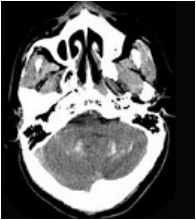

[单选题]男,7岁,无明显症状,CT如图所示,最可能的诊断是()A.上颌窦淋巴瘤B.上颌窦炎C.上颌窦粘膜下囊肿D.上颌窦乳头状瘤E.鼻炎及副鼻窦粘膜下囊肿